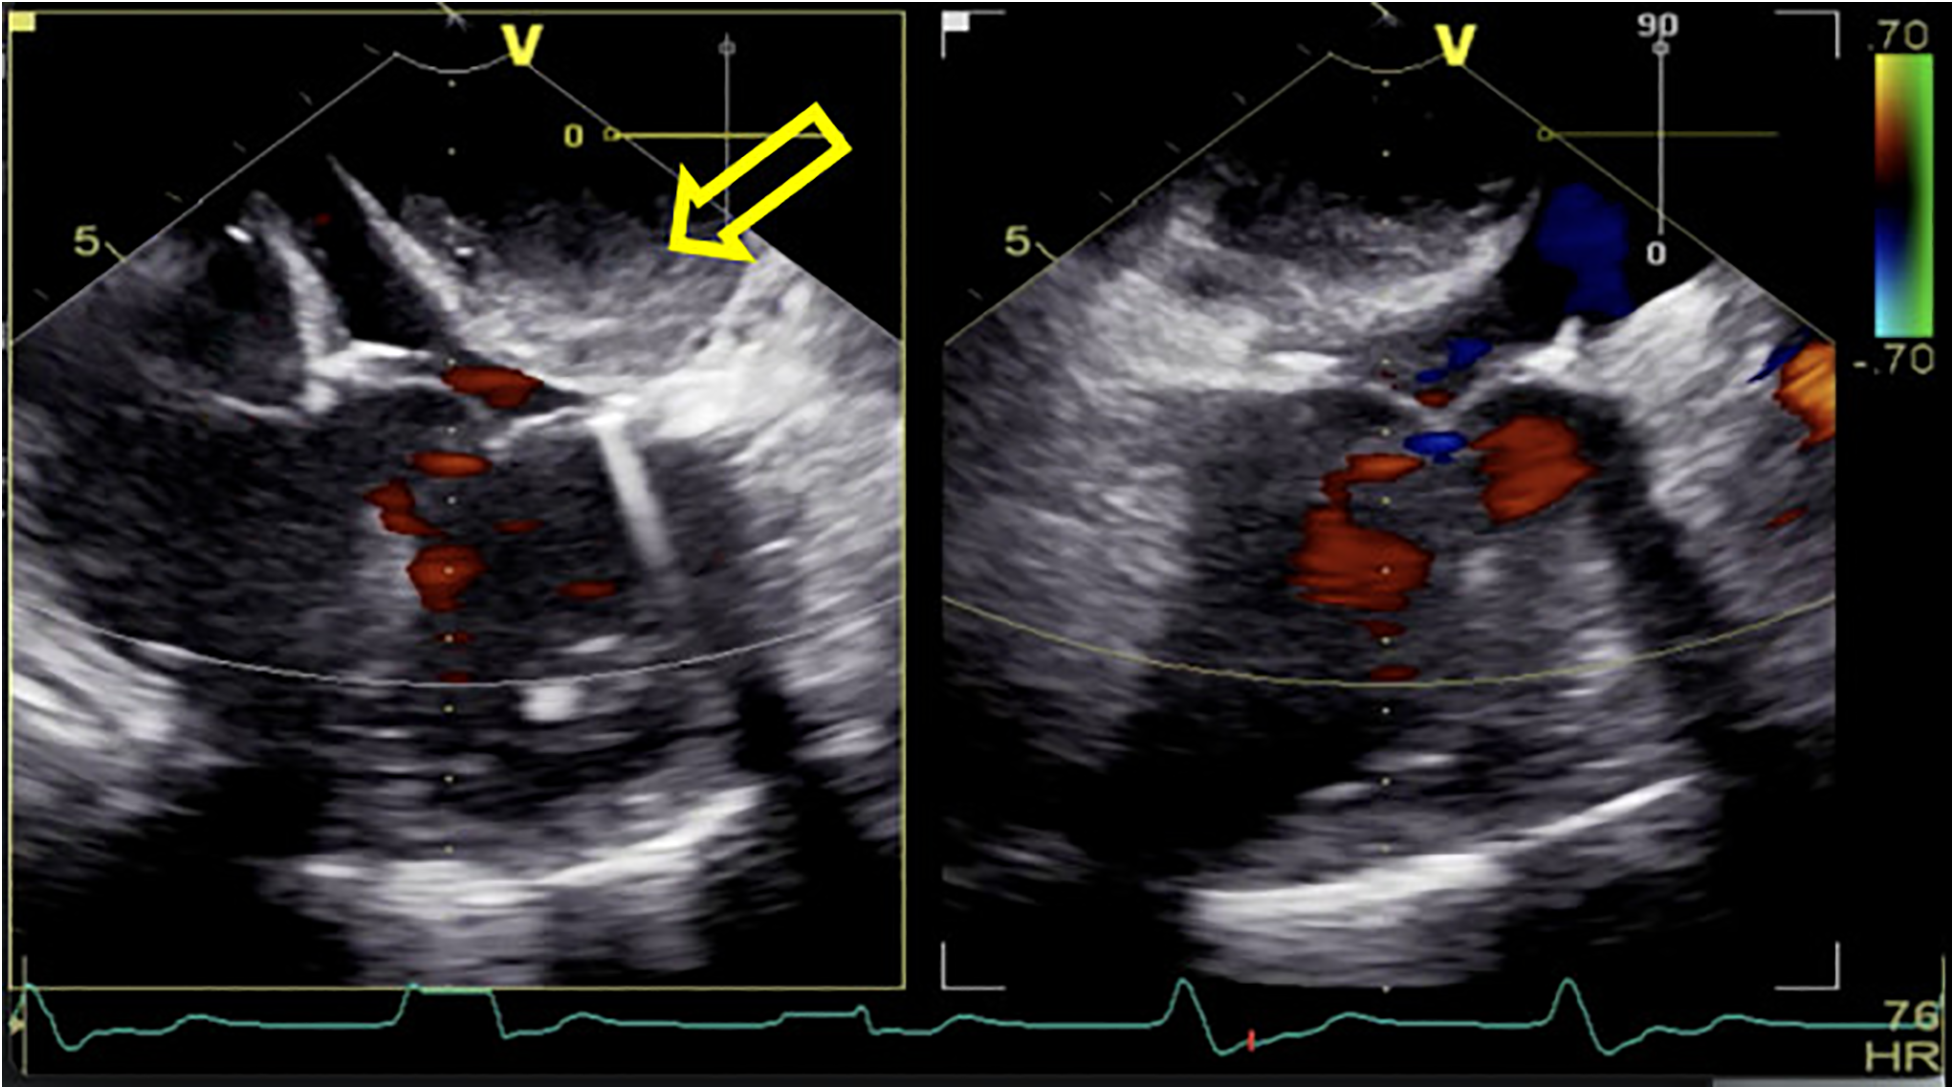

Following routine cardiac general anesthetic procedures, TEE confirmed severe eccentric mitral regurgitation owing to prolapse of the middle scallop of the posterior mitral leaflet along with light tricuspid regurgitation and pulmonary valve regurgitation. The patient's left ventricular ejection fraction (LVEF) was normal (65%). A median sternotomy was performed, followed by standard right atrial and atrial septum access. Mitral valve replacement involved continuous suturing with 2-0 prolene thread, placement of a size 29 bioprosthetic valve, and ligation of the left atrial appendage with double 10-0 sutures. Subsequently, the aortic root was thoroughly deaired under TEE guidance, the aortic clamp was released, and the heart spontaneously started to re-beat. Unexpectedly, during the hemostasis process, the patient's blood pressure gradually decreased, requiring an increase in the dosage of adrenaline and noradrenaline to maintain an appropriate level. At this time, there was no obvious blood loss spots; we also excluded the possible use of medications such as protamine or antibiotics that could have triggered allergic reactions. To determine the cause of hypotension, we conducted an investigation using TEE and discovered a hematoma on the posterior wall of the left atrium, measuring approximately 3 × 4 cm in diameter (Figure 1). This hematoma was rapidly expanding and gradually compressing the mitral valve annulus.

Figure 1. After being weaned from CPB, a rapidly increasing left atrial dissection hematoma (indicated by the yellow arrow) was visible in the posterior atrioventricular groove of the left atrial posterior wall. It gradually compressed the mitral valve annulus, causing relative stenosis of the left ventricular inflow tract.

Given this emergent situation, cardiopulmonary bypass was reinitiated to resolve the circulation crisis. The results of TEE monitoring showed that the left atrial dissection hematoma was compressing the left ventricular inflow tract, which accelerated blood flow through the mitral valve, causing mitral valve relative stenosis. In addition, TEE found pulsatile blood flow in the hematoma at the left atrioventricular groove on the posterior wall of the left atrium after the second cardiopulmonary bypass (Figure 2), suggesting that this blood flow was related to the left coronary circumflex branch. However, the relationship between the left circumflex branch and the dissection could not be determined. Because the criminal's blood flow (blood vessels) was located in the posterior atrioventricular groove and could not be explored through a surgical incision, we ultimately decided to incise the left atrial endocardium to drain the decompression hematoma through the left atrium (Figures 3, 4). The specific method applied was to reopen the right atrium and atrial septum along the original surgical incision. After confirming the correct position of the artificial valve and the integrity of the left atrial endocardium, the latter was incised for drainage and decompression, and the atrial septum and right atrium were resutured. The patient was admitted to the ICU for further management and discharged home after 16 days.